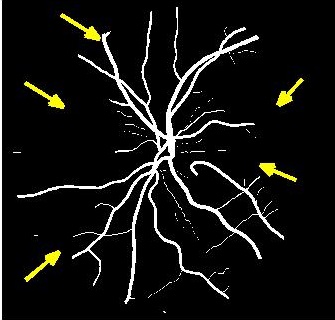

Results of fold cross validation for are presented in Table 1. Due to space constraints only SSIM values are shown for . For , performance difference of all methods is small but becomes more pronounced for higher . gives the best results for all , and the improvement over competing methods is significant as is evident from the values of Wilcoxon signed-rank tests. Figure 3 shows results of the top methods (due to space constraints) for . shows the best performance as is evident from the SR image in Fig. 3 (b) where one of the minor retinal branches (indicated by yellow arrow) is clearly visible. On the other hand the SR image by (Fig. 3 (c)) is blurry and does not clearly show this retinal branch. Other methods perform much worse, with significant blur visible for the main branches as well. Clearly, gives the closest reconstruction to the HR image of Fig. 3 (a).

4.2 Retinal Blood Vessel Segmentation Results

We present retinal vessel segmentation results on the DRIVE [16], STARE [6] and CHASEDB1 [5] datasets with , and images respectively. Original images and manual annotations () are downsampled by to get and sets of from methods trained on [2]. and the sets of were used to train different state-of-the art U-Nets for vasculature segmentation [1]. The average accuracy () and sensitivity () for is summarized in Table 2. Better ISR methods should give higher vessel segmentation accuracy and performance of gives a lower bound on the segmentation error. ’s performance is closest to , and establishes its superiority over all competing methods. Figures 4 (a)-(h) show results of vessel segmentation on an example image. ’s performance is most similar to as is evident from the areas of inaccurate segmentation highlighted by yellow arrows. Most of the methods do not segment the finer vasculature structures, while SSR and SR-RF are unable to segment some of the major arteries.